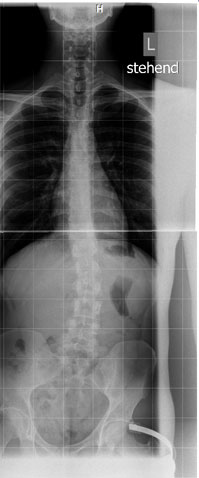

Ich muss sagen, wenn ich das aktuelle Bild mit denen von 2006 vergleiche (hier kann ich nur "Rückgriff" auf meine Erinnerungen bzgl. der Aufnahmen nemen, aber habe ja den Befund von damals vorliegen s.o.), so ist es subjektiv sogar BESSER! geworden. Ich kann auf den Röntgenaufnahmen in der oberen Hälfte meiner Wirbelsäule keine deutliche Verkrümmung erkennen. In der unteren Hälfte vermag ich in jedem Falle eine recht deutliche Skoliose und einen Beckenschiefstand zu erkennen.

Anbei das Röntgenbild vorhin. Was meint ihr? Ist es im Vergleich zu meinem damaligen Befund besser/schlechter/unverändert geblieben? Wie hoch meint ihr ist der Cobb-Winkel?

Man kann unmöglich einen Befund ohne Winkelangaben mit diesem Röntgenbild vergleichen. Bei Winkel-Abschätzungen halte ich mich generell zurück. Aber besonders "schlimm" finde ich es nicht.Anbei das Röntgenbild vorhin. Was meint ihr? Ist es im Vergleich zu meinem damaligen Befund besser/schlechter/unverändert geblieben? Wie hoch meint ihr ist der Cobb-Winkel?

Jedoch scheint mir auf dem Röntgenbild die BWS recht grade zu sein und der Bogen in der LWS ist ja auch nicht sonderlich stark.

Wahrscheinlich sind es bei dir eher die Beckenschiefstellung und die Spondylose die Probleme bereiten?!